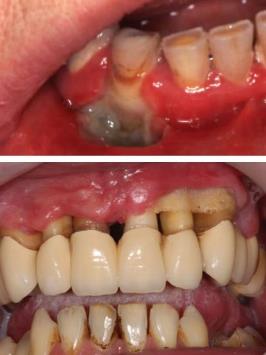

Bár ez igazán nem gyakori betegség, a leggyakoribb klinikai megjelenése az agranulocytosis. Ez a betegség a periférián a granulocytaszám csökkenésében manifesztálódik. Ennek következtében nő a beteg fogékonysága a különböző bakteriális fertőzésekre. A szájnyálkahártyán ez különböző, a normál flórához tartozó baktériumok okozta opportunista fertőzésekhez és a szájnyálkahártya bármely részén, de elsősorban a gingiván kialakuló gyulladásmenetes udvarral szegélyezett fekélyképződéshez vezet (15.6. ábra). Ezek az elváltozások klinikailag néha nem különböznek a leukaemiában kialakuló képtől, de ilyenkor soha nem fordul elő ínyduzzanat. A betegségek etiológiai folyamata hasonló a fehérvérsejtek védő funkcióját tekintve, egyik esetben a funkciót vesztett, malignus fehérvérsejtszám jelentős emelkedése vagy a funkcióképes leukocyták teljes hiánya (lásd paramyeloblastos akut leukaemia), másik esetben a normál fehérvérsejtek elégtelen termelése vagy azok gyors pusztulása (lásd gyógyszer okozta citotoxikus reakciók) az ok.

15.6. ábra. Agranulocytosis – gyulladásmentes mély fekély a gingiván

(Gera I. felvétele)